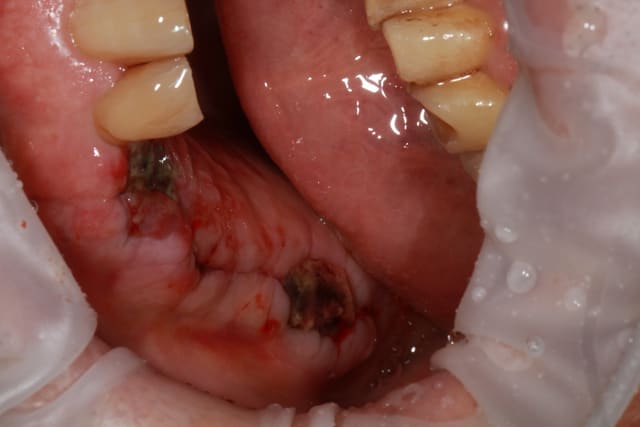

09/10/2013 à 18h33

vue à 8 jours

les photos